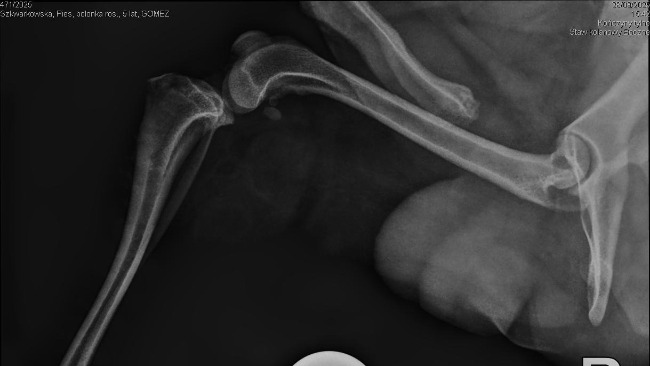

Gomez ma już za sobą dwie poważne operacje — dzielnie zniósł wszystko, mimo trudnych chwil i wielu ograniczeń. Każdy dzień to walka o jego sprawność, komfort i powrót do normalności.

Od poniedziałku zaczynamy rehabilitację, która będzie kluczowa w jego dalszym leczeniu. Przed nami długa droga, pełna wyzwań, ale też nadziei.